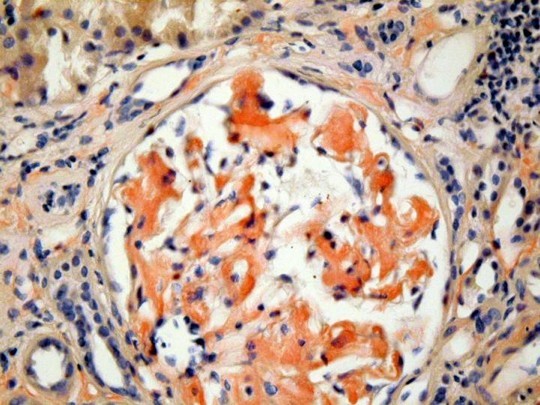

RW is a 60 yr old male who has been on renal dialysis for the past 15 years. His urinary protein electrophoresis is notable for light chains. Based on his history and the histology below, what is his diagnosis?

Amyloidosis–> Glomerulonephritis:

A collection of diseases sharing a common feature:

- common feature = Extracellular deposition of pathologic insoluble fibrillar proteins

- Protein deposition impairs normal function

Multiple organs and tissues can be involved

Virchow coined the term amyloid, meaning starch like

** Chronic Renal dialysis–> alpha-2-beta globulin deposition

Histo:

Light microscope:

- Amorphous deposition of pink material around glomeruli, afferent, efferent arterioles

- Congo red positive, Not PAS positive

Immunofluorescence:

- Non-specific staining with Ig reagents